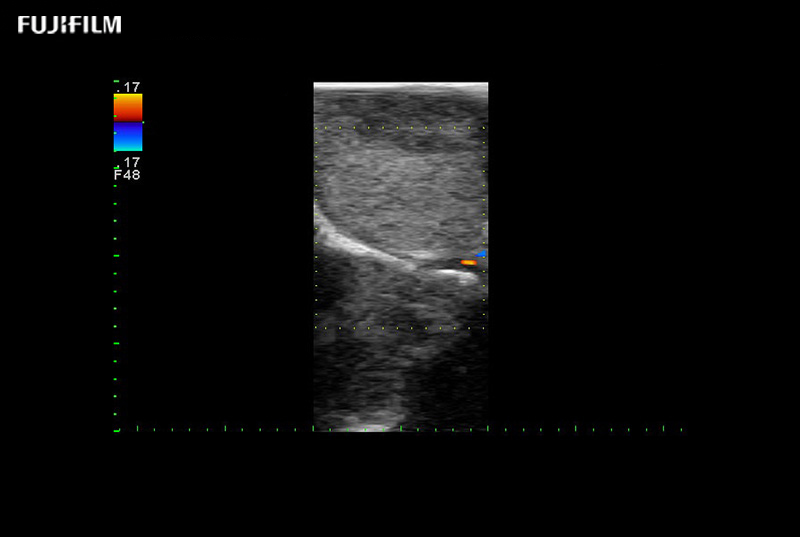

Hockey-stick linear array transducer is the transducer of choice for cervical spine scanning.

Main Specifications:

Exclusive 10mm side‐fire linear array transducer with 2.87mm diameter is ideal for real‐time visualization through and behind structures and instant, scalable definition of anatomy and vascularity including the ability to delineate and define tumor margins.